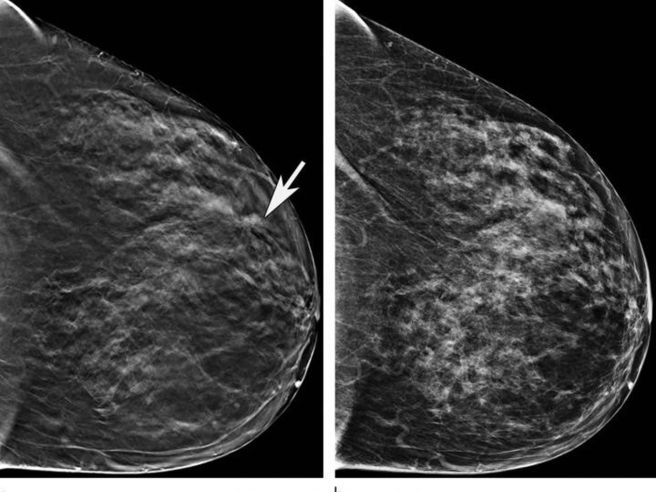

Almudena Quintana Morgado, directora general Asistencial del Servicio Madrileño de Salud (Sermas), ha asegurado la eficiencia del Programa de Detección Precoz del Cáncer de Mama (DEPRECAM) en Madrid, destacando que no hay listas de espera estructurales y que el tiempo medio de espera es de 34 días para realizar una mamografía, garantizando además que todas las pacientes son informadas sobre los resultados de sus pruebas.

Según la directora, los resultados de las pruebas son comunicados en menos de 30 días, y en caso de resultados sospechosos, la derivación al hospital se produce en aproximadamente 13,7 días. Ha destacado la transparencia y la seguridad del programa al asegurar que todas las mujeres reciben información detallada sobre el estado de su mamografía.

Durante 2023, el programa ha detectado 2.576 casos sospechosos de cáncer, requiriendo pruebas adicionales para confirmar el diagnóstico. Además, la tasa de detección de cáncer está en 5,4 casos por cada mil mujeres examinadas, con un alto porcentaje de detección en estadios iniciales, lo que facilita tratamientos menos invasivos y mejora las tasas de curación.